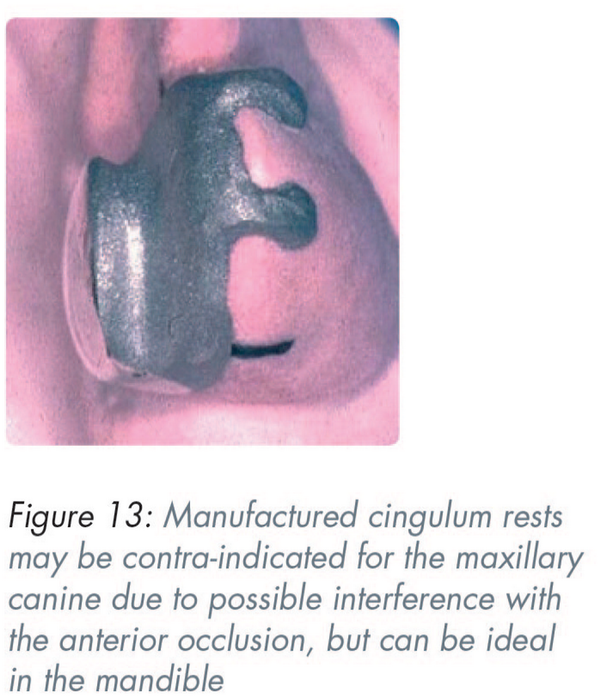

The inclined lingual surfaces of anterior teeth present problems with the provision of positive rest seats. The maxillary canine with a prominent cingulum may have an adequate thickness of enamel to allow the depth that a rest seat preparation requires. However similar preparations involving the mandibular canine are likely to cause dentine exposure. It is preferable to make rests with bonded etched metal, bonded composite resin or as part of a crown. Manufactured cingulum rests may be contra-indicated for the maxillary canine due to possible interference with the anterior occlusion but can be ideal in the mandible (Figure 13).